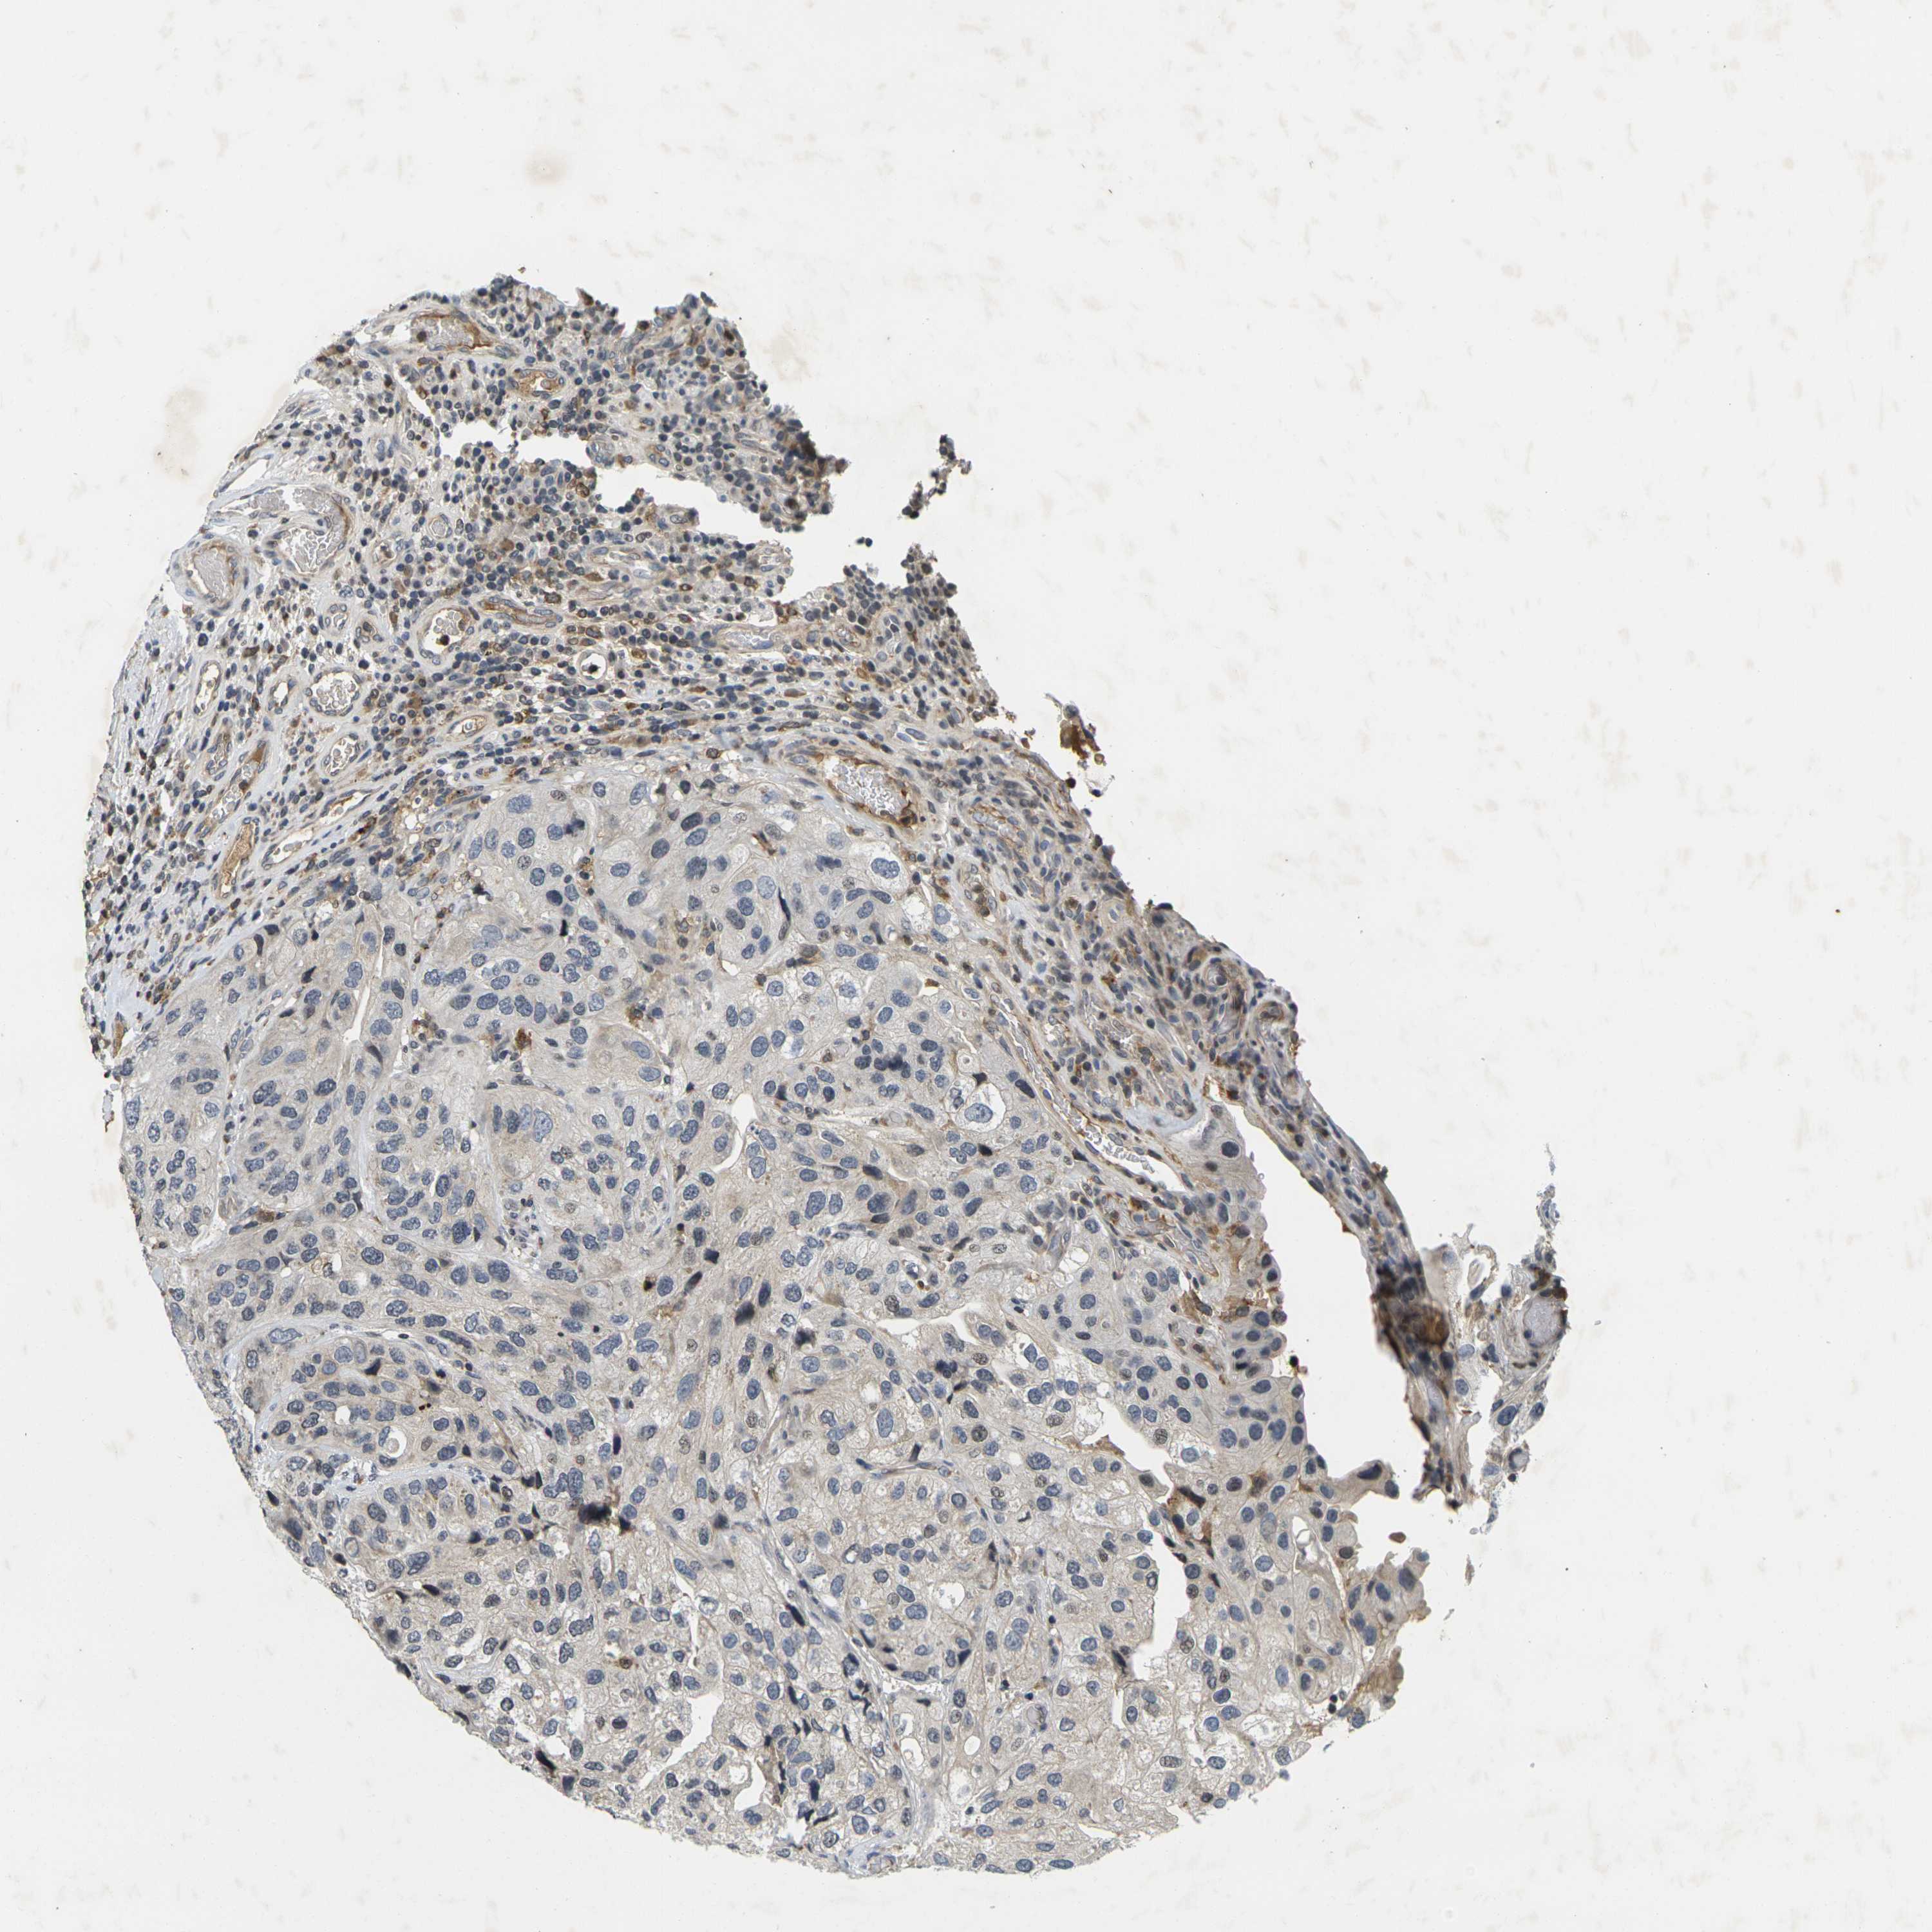

UROTHELIAL CANCER - Protein expressioni

A mouse-over function shows sample information and annotation data. Click on an image to view it in a full screen mode. Samples can be filtered based on level of antibody staining by selecting one or several of the following categories: high, medium, low and not detected. The assay and annotation is described here.

Note that samples used for immunohistochemistry by the Human Protein Atlas do not correspond to samples in the TCGA dataset.

Antibody stainingi

Antibody staining in the annotated cell types in the current human tissue is reported as not detected, low, medium, or high, based on conventional immunohistochemistry profiling in selected tissues. This score is based on the combination of the staining intensity and fraction of stained cells.

Each image is clickable and will lead to virtual microscopy that enables deeper exploration of all samples and also displays staining intensity scores, fraction scores and subcellular localization as well as patient and tissue information for each sample.

Antibody HPA001471

Antibody CAB009828

Staining

High

Medium

Low

Not detected

Intensity

Strong

Moderate

Weak

Negative

Quantity

>75%

75%-25%

<25%

None

Location

Nuclear

Cytoplasmic/membranous

Cytoplasmic/membranous,nuclear

Urothelial carcinoma, High grade